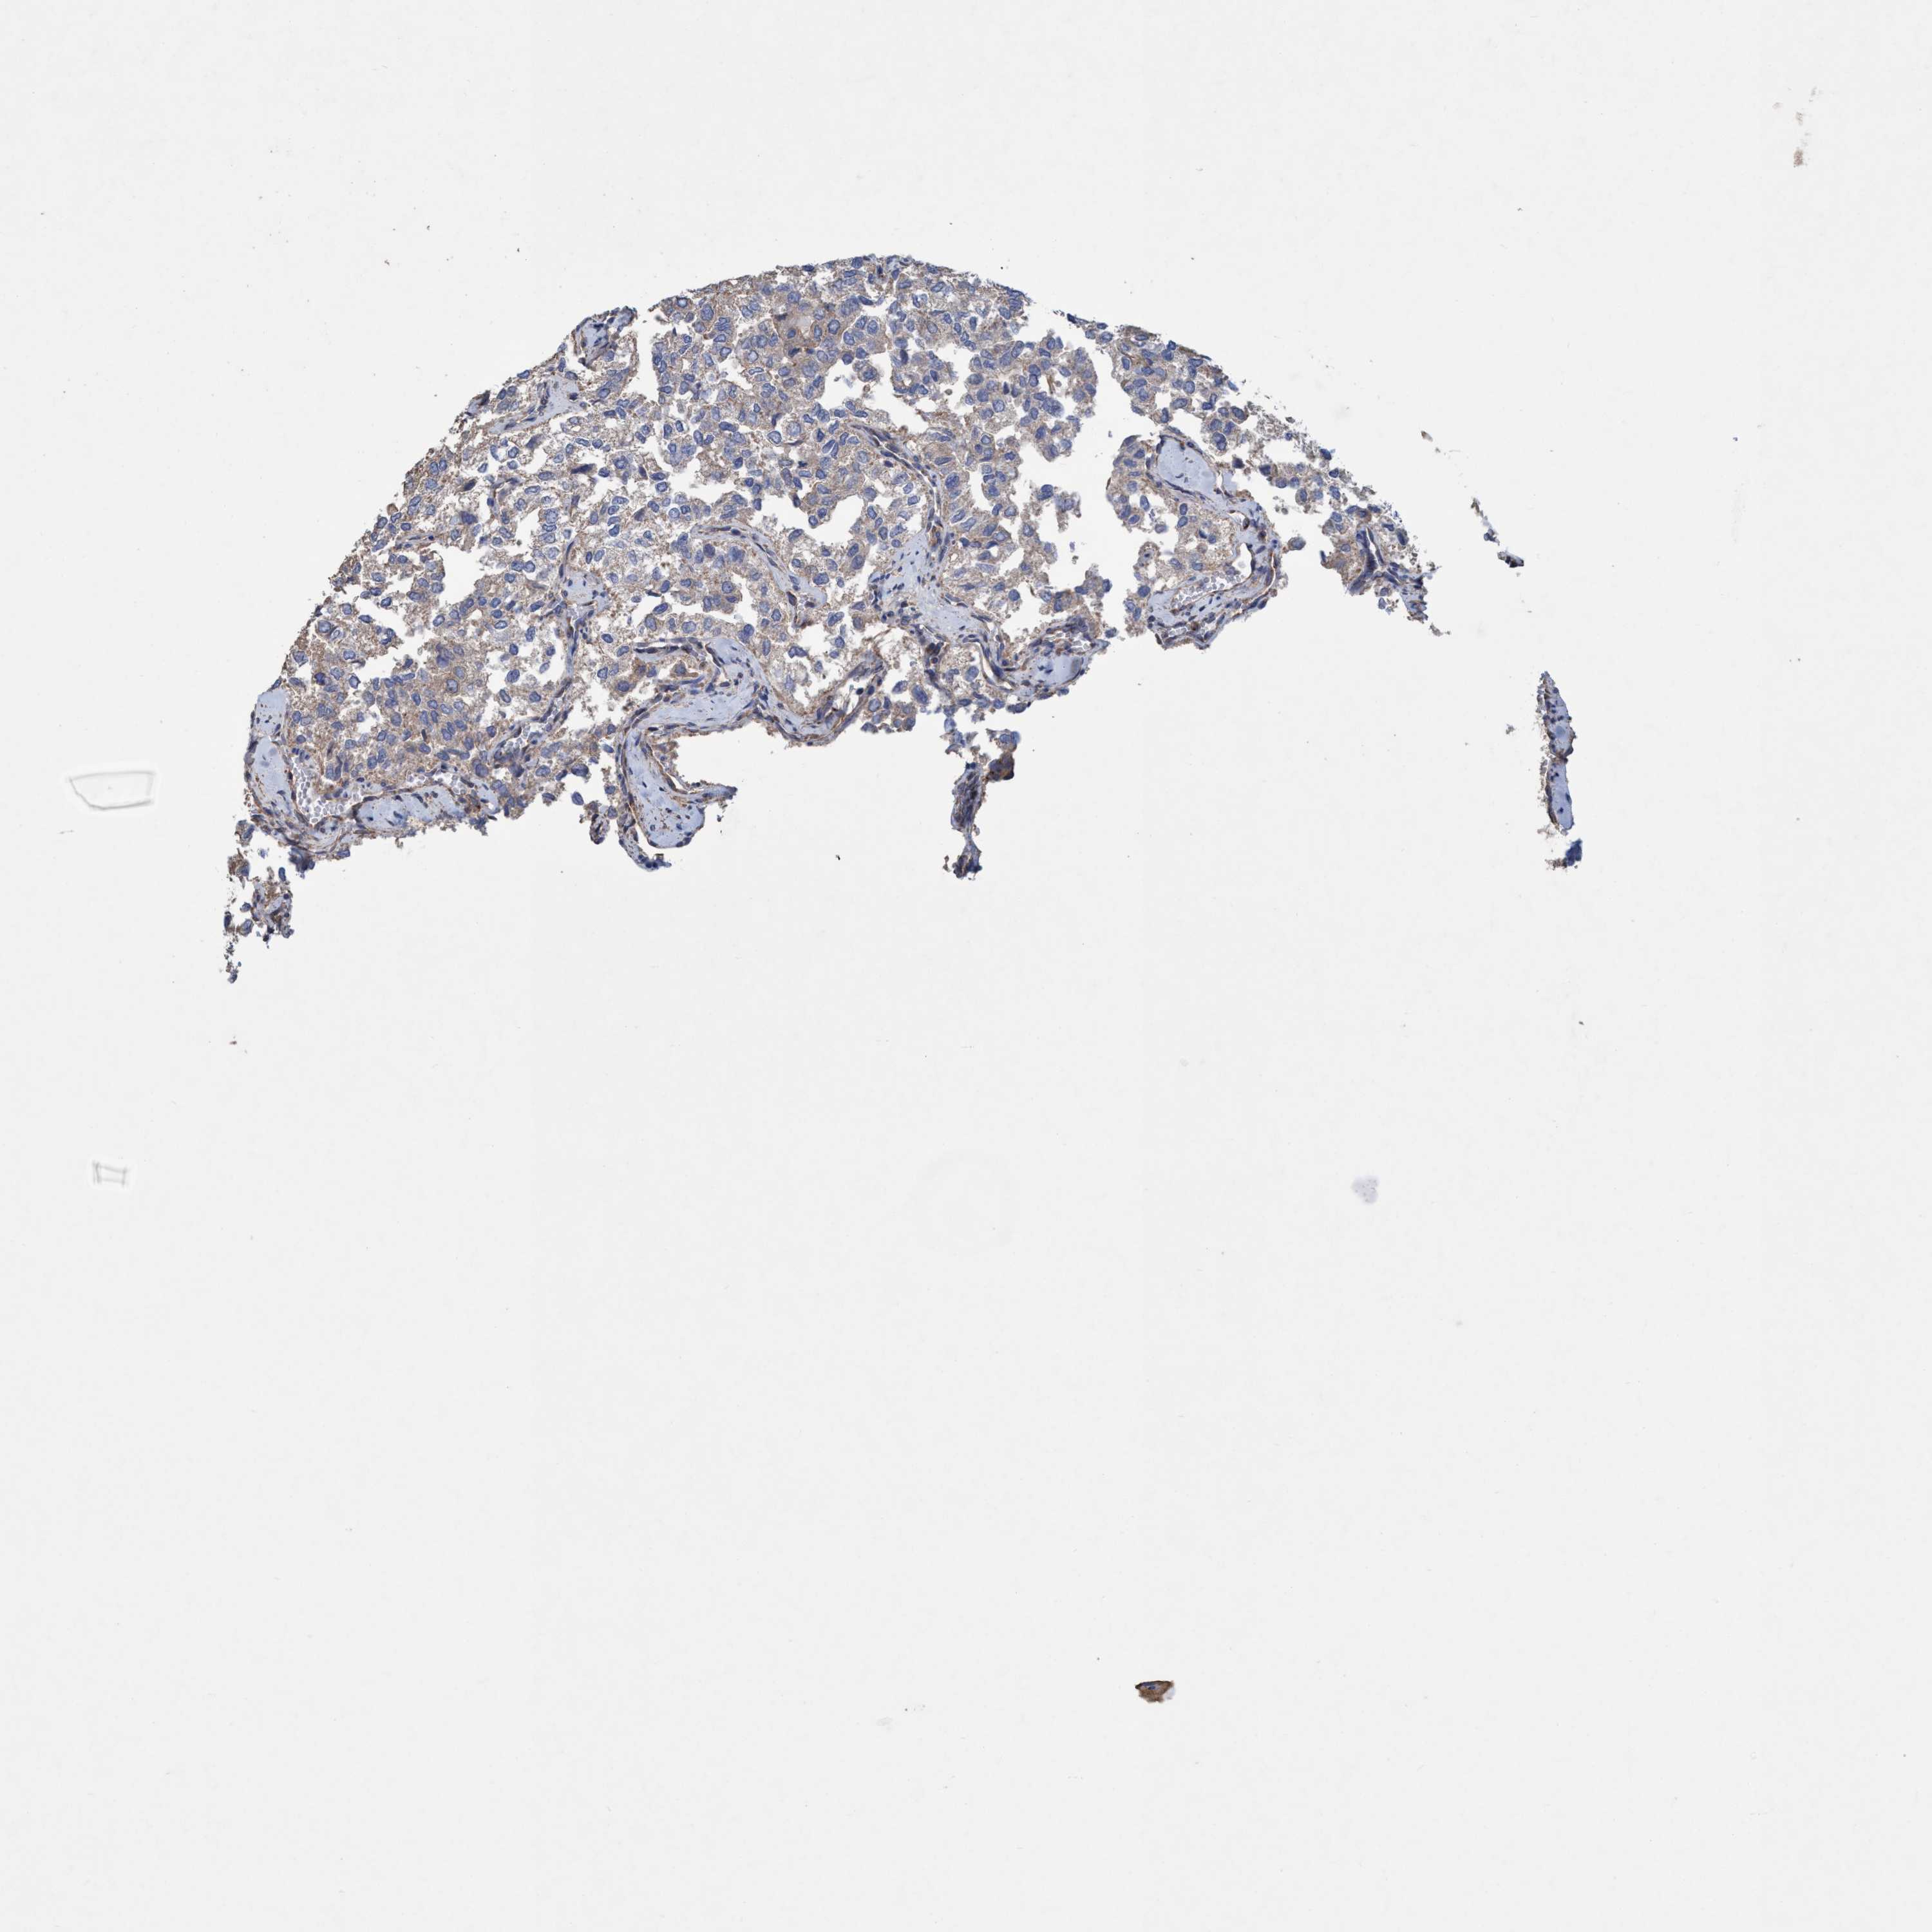

THYROID CANCER - Protein expressioni

A mouse-over function shows sample information and annotation data. Click on an image to view it in a full screen mode. Samples can be filtered based on level of antibody staining by selecting one or several of the following categories: high, medium, low and not detected. The assay and annotation is described here.

Note that samples used for immunohistochemistry by the Human Protein Atlas do not correspond to samples in the TCGA dataset.

Antibody stainingi

Antibody staining in the annotated cell types in the current human tissue is reported as not detected, low, medium, or high, based on conventional immunohistochemistry profiling in selected tissues. This score is based on the combination of the staining intensity and fraction of stained cells.

Each image is clickable and will lead to virtual microscopy that enables deeper exploration of all samples and also displays staining intensity scores, fraction scores and subcellular localization as well as patient and tissue information for each sample.

Antibody HPA023013

Antibody HPA024452

Staining

High

Medium

Low

Not detected

Intensity

Strong

Moderate

Weak

Negative

Quantity

>75%

75%-25%

<25%

None

Location

Nuclear

Cytoplasmic/membranous

Cytoplasmic/membranous,nuclear

Papillary adenocarcinoma, NOS

Follicular adenoma carcinoma, NOS